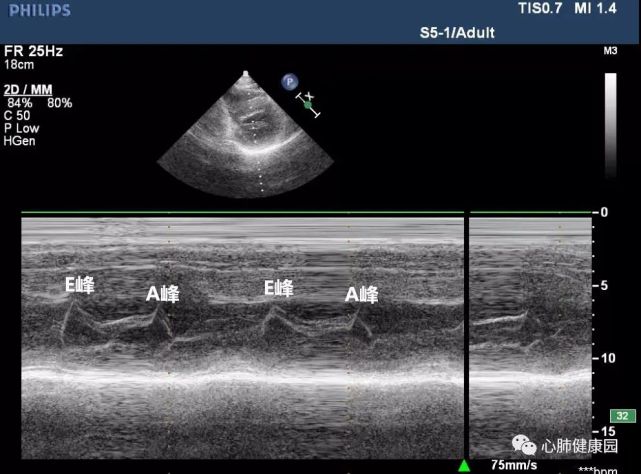

二尖瓣狭窄与二尖瓣关闭不全心脏彩超报告解读

二尖瓣狭窄与二尖瓣关闭不全|心脏彩超报告解读